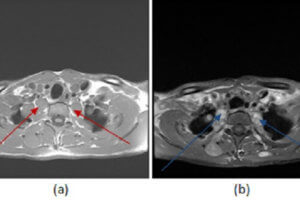

Parotid Lymphoma

Parotid masses are often seen incidentally on CT scans of the brain and neck. The most common primary parotid mass is the benign mixed tumor (also known as a pleomorphic adenoma). These... Read more »